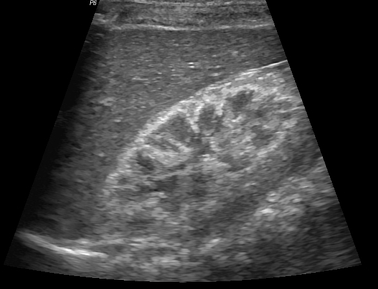

Néphrocalcinose médullaire

- Accentuation de la différenciation cortico-médullaire avec hyperéchogénicité médullaire

- Hyperparathyoridie ++ (effet de l’hypercalcémie)

- Sinon acidose rénale tubulaire

- Sur Reins médullaires en éponge

Mnemotechnique HAM - Hyperparathyroidie - Acidose Rénale Tubulaire - Medullary sponge kidney